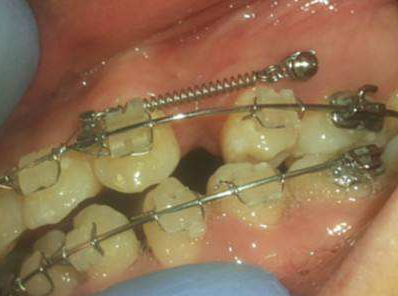

骨釘,顧名思義,是一種外形十分像釘子的種植釘,是放置在牙骨上方一個迷你的"釘子"。

它體積的小,好植入,近年來,逐漸成為正畸科常用的正畸輔助工具。

但是有了骨釘植入,就可以解決前者調(diào)節(jié)方案的煩惱,可以根據(jù)不同的調(diào)節(jié)方案,不同的調(diào)節(jié)需求,在口腔中相應(yīng)的位置植入骨釘形成口腔中的一個受力點,同時利用正畸器,橡皮筋相互拉力的作用下,更好的幫助醫(yī)生更好的控制牙齒的移動,做到"該移動的牙移動,不該動的牙不動"從達到佳的調(diào)節(jié)果。